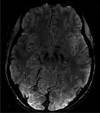

Recent developments in brain imaging methods are on the verge of changing the evaluation of people with Parkinson's disease (PD). This includes an assortment of techniques ranging from diffusion tensor imaging (DTI) to iron-sensitive methods such as T2*, as well as adiabatic methods R1ρ and R2ρ, resting-state functional MRI, and magnetic resonance spectroscopy (MRS). Using a multi-modality approach that ascertains different aspects of the pathophysiology or pathology of PD, it may be possible to better characterize disease phenotypes as well as provide a surrogate of disease and a potential means to track disease progression.